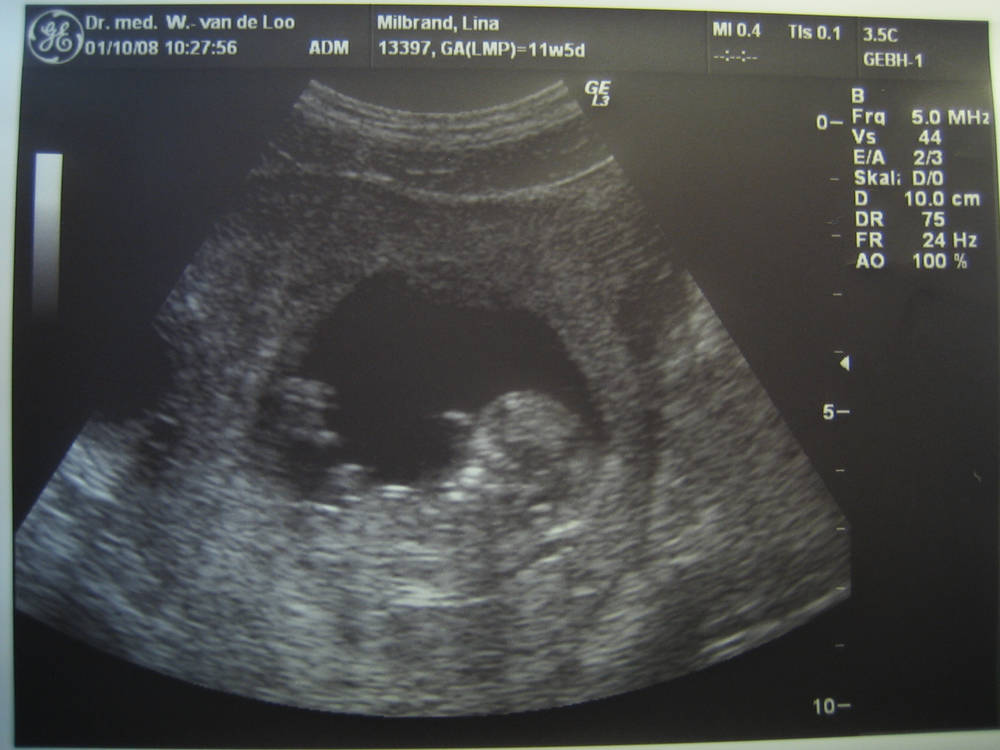

Lotte Hedwig Hoppe (* 11.04.2009) zu Frida